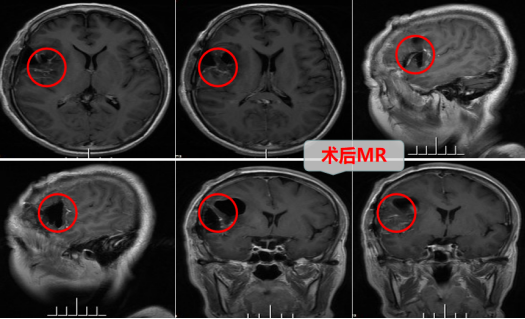

术中,医生团队利用神经导航、荧光显影等先进技术,在高清智能显微镜放大下,仔细精准地操作,小心分离并逐渐安全切肿瘤,术中出血很少,成功安全切除了肿瘤。术后朱女士神志清醒,因术中脑组织及周围血管保护良好,术后第三天朱女士可下床少量活动,能自行康复锻炼,无癫痫发作,无构音障碍,无肢体无力、感觉障碍等,恢复良好。